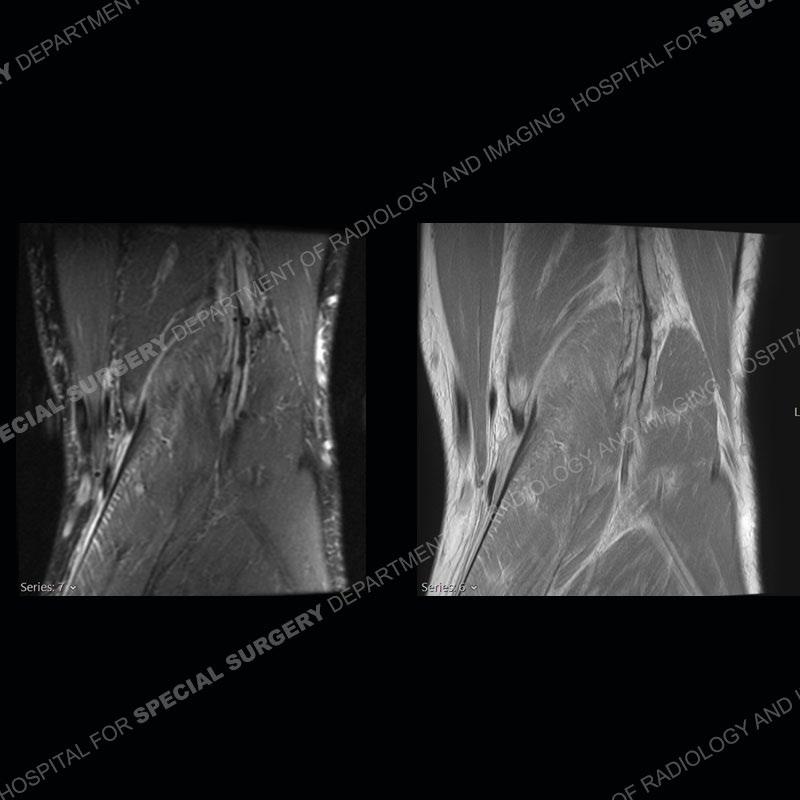

Findings

The radiographs show degenerative change of the medial compartment and a varus knee, but they are not germane to this case. No acute bony injury is present. The MRI shows edema of the posterior medial knee/soft tissue and a focal area of a partially disrupted low signal structure. The details are kept at a minimum in the findings of this case on purpose.

Diagnosis: Partial Disruption Medial Head Gastrocnemius (MHG)

The findings were kept purposefully vague as identifying the structures early on takes away a lot of the diagnosis. An uncommon entity and one of which we do not see a lot. Enthesopathic changes and tendinosis are seen as are distal MHG injuries, but proximal tears are rarely present. This case highlights a number of points. One, it almost always comes down to anatomy. Perhaps not a structure we normally spend too much time on, except save for diagnosing a Baker’s cyst, but knowing where this structure and all structures exist in all three planes is imperative. Second, when you think you are making a “call” or finding that you have never made before, step back and think is this just the abnormal presentation of a common pathology. That situation arises much more frequently. Third, if you look at it once, twice, and probably a third time and are confident in your odd or very rare diagnosis, stick to your guns. Especially, when it comes down to anatomic structures, the proof will be in the images.

Fourth, use all imaging planes and different pulse sequences to make your diagnosis. The edema highlighted in this case can be seen as the obscuration of fat on the PD images but is much easier to perceive as the high signal on the IR pulse sequences. The actual disruption of the MHG myotendinous junction is only able to be seen on the axial images. On the sagittal and coronal images, we get a sense something is wrong but hard to be exact. Lastly, when you look at a study and something just seems off (as I would say the sagittal and coronal images do with that dark band of tissue posteriorly), listen to yourself and go through the study slowly and meticulously. Most of the time you will find you were right, and something indeed is present.